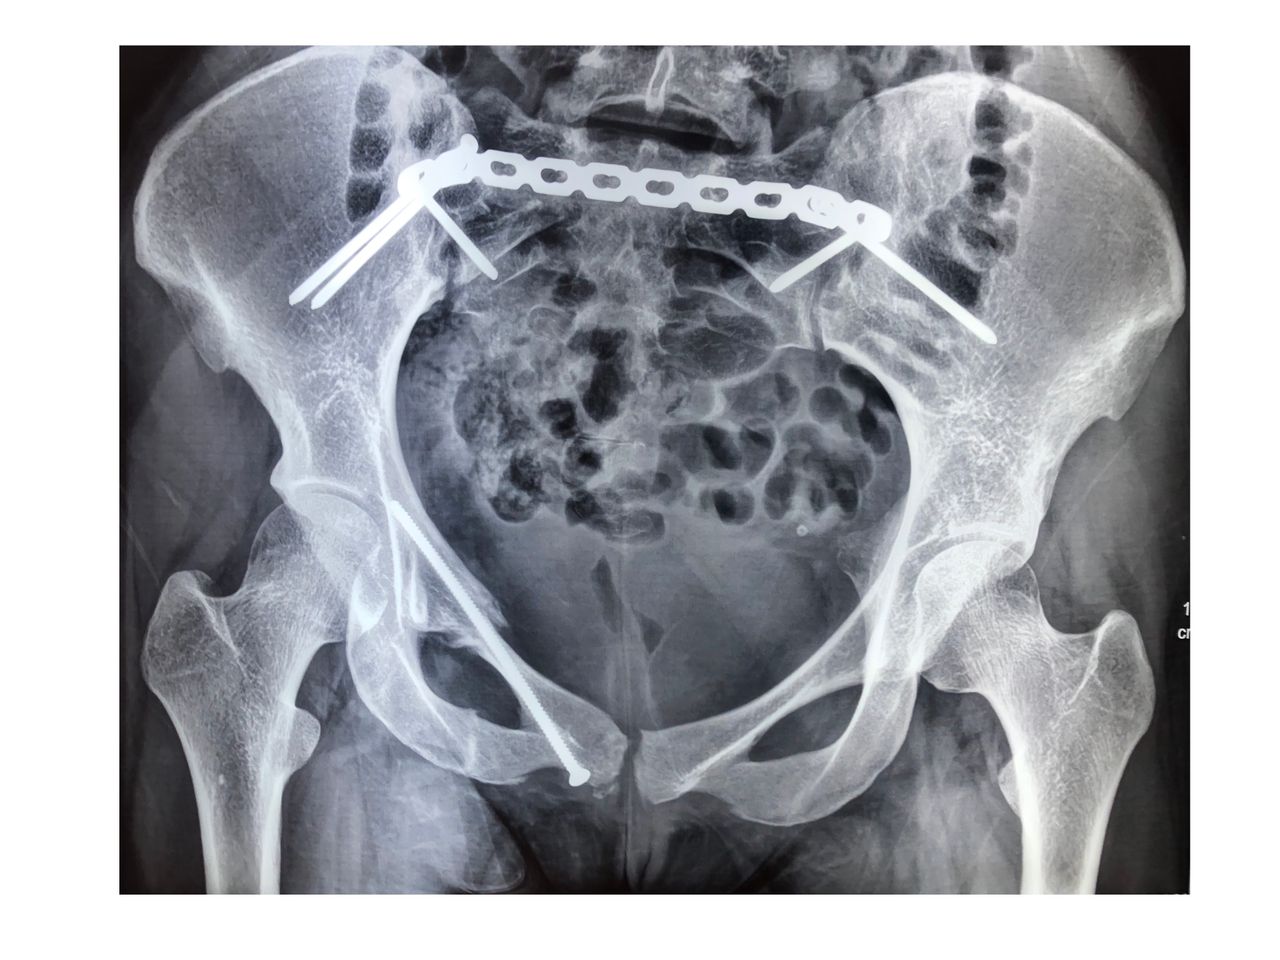

Cirugía ortopédica y traumatológica en el paciente politraumatizado (politrauma, pelvis y acetábulo). Cuenta UNAM Unidad Médica de alta Especialidad Hospital de Traumatología y Ortopedia Lomas Verdes IMSS

• Reparación de fractura de anillo pelviano con abordaje doble